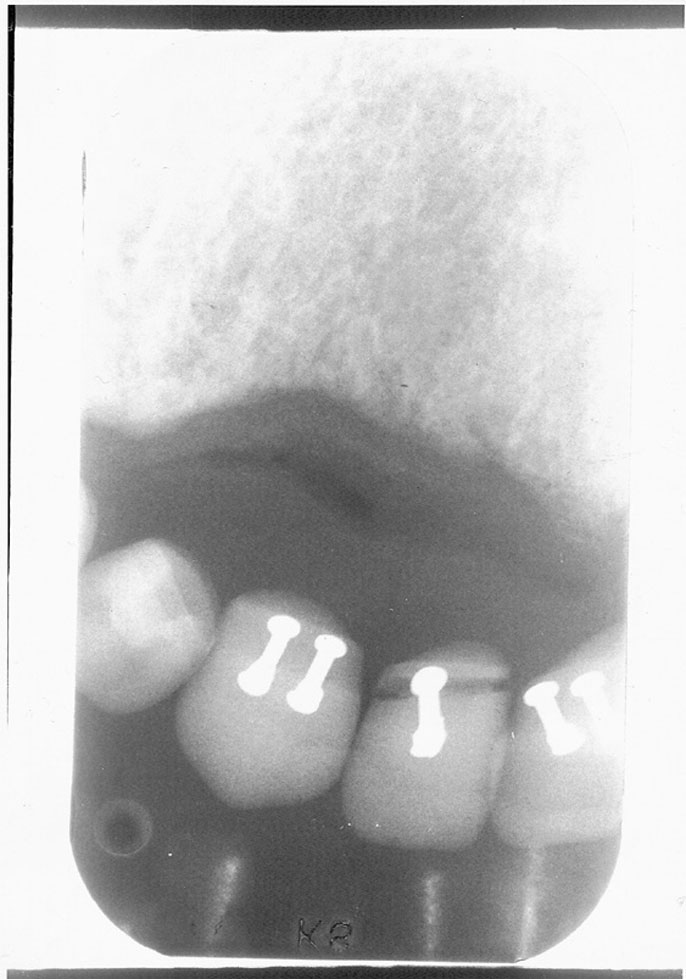

Figure 1. Double exposure.

Figure 1

Double Exposure

Description: Double exposures occur when the same film is used for more than one exposure (Figure 1). This can occur if the operator confuses an exposed film with an unexposed film and places the packet into the patient’s mouth as if it were unused. Double exposures can also result from activating the exposure button twice.

Differential Diagnosis: The resulting film is dark because it has technically been overexposed, resulting in confusing, overlapped anatomic images.

Consequences: Retakes are almost always necessary because of the lost detail caused by anatomic superimpositions. Fortunately, double use of a packet usually occurs with the same patient in the chair; but if a previously exposed film from one patient were placed into the mouth of another, the operator would be running the risk of cross-contamination and transmitting disease between patients.

Remedy: After a film packet has been exposed the op­erator should place the film into a lead receptacle. Unexposed films and exposed films should never be kept in the same area.